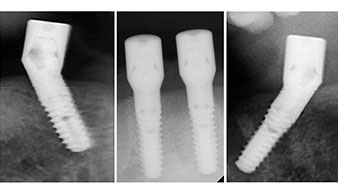

A three-dimensional cone beam computed tomography scan (CBCT, Planmeca) was performed to aid planning and minimize risks. This revealed that the quality and quantity of the available bone were sufficient for the surgery and immediate restoration using the Fast & Fixed method. Following the protocol for this concept, the implants are inserted at 35, 32, 42 and 45. Angling the distal implants by up to 45° shifts the emergence profile to posterior and generates a larger support polygon (Fig. 3).

This corresponds to the next preset position in the Implantmed. Here we see the W&H contra-angle handpiece being held at a 45° angle to mesiocaudal in the region of 45 in order to preserve the mental nerve. The mental foramen is used as the anatomic reference for all drilling in this region. The subsequent holes were drilled at a reduced speed of 300 rpm (Fig. 10 and 11).

The light increases the contrast in the oral cavity and improves visual perception. Both the contra-angle handpiece and the S-11 straight handpiece from W&H are externally cooled, which can be seen as a great advantage because the saline solution arrives exactly where it’s needed and can also be subsequently adjusted if necessary. The contra-angle and straight handpieces can be dismantled, which is highly recommended for hygiene and sterilizability. Four SKY implants measuring 4.0 x 14mm were placed.